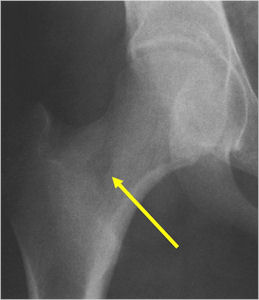

Sites:

- Femoral neck most common but can occur in any bone and any site within a bone (metaphyseal, diaphyseal, epiphyseal; cortical, medullary and periosteal)

- 50% occur in long bones of lower extremities

- Most osteoid osteomas are intracortical in origin but can also occur in the medullary canal or subperiosteal

- Intracapsular osteoid osteomas are difficult to identify because there is no periosteum in the intracapsular region and hence a periosteal reaction does not occur.